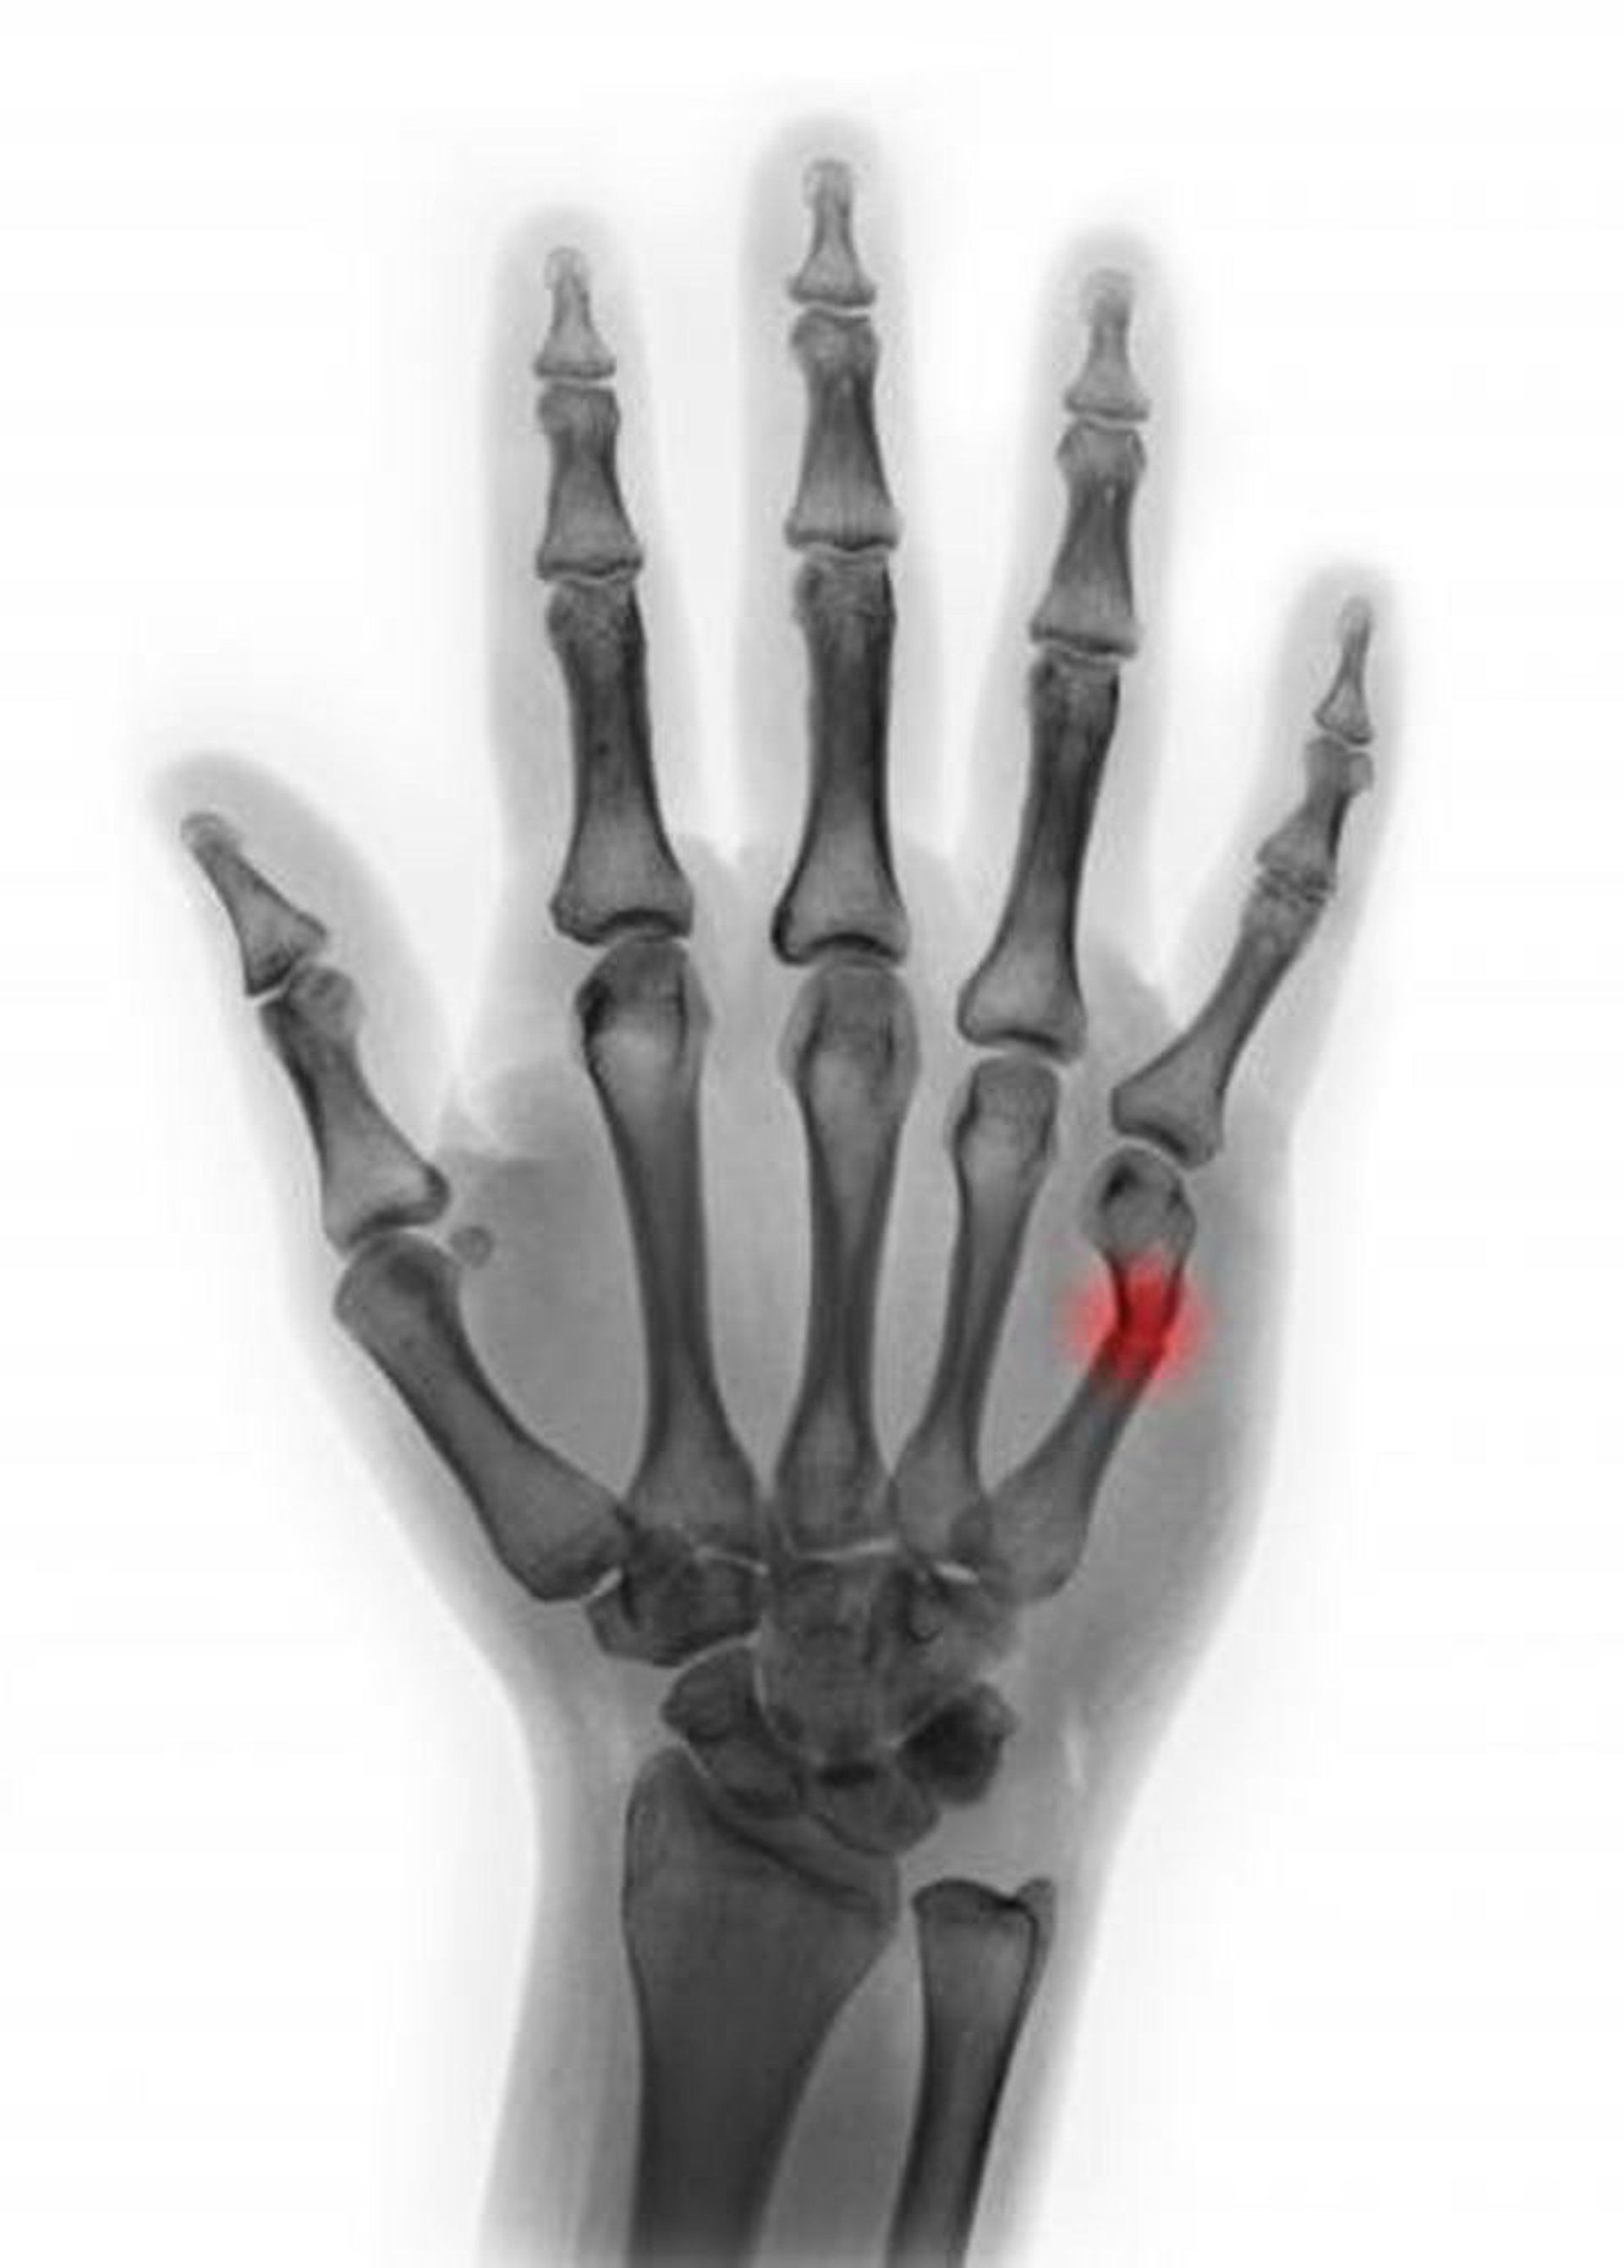

Fractura del 5° cuello de los metacarpianos

Esta radiografía coloreada muestra una fractura del cuello del quinto metacarpiano. En esta vista, la angulación parece ser < 45°, lo que sugiere que la reducción no es necesaria.

SCOTT CAMAZINE/SCIENCE PHOTO LIBRARY